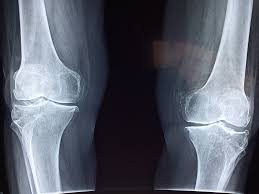

La menace silencieuse pour votre squelette

Un aspect méconnu des sodas, particulièrement des colas, concerne leur influence sur la robustesse de notre structure osseuse. Le danger ne réside pas dans un composant spécifique, mais plutôt dans le fait qu’ils remplacent souvent des boissons riches en calcium essentielles, comme le **lait ou les alternatives végétales enrichies**. Pour les adolescents et jeunes adultes, cette substitution peut compromettre l’édification d’une **masse osseuse solide**. Chez les adultes, elle peut participer à une **détérioration progressive** de la densité osseuse au fil du temps.